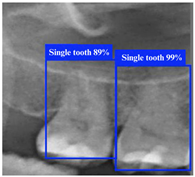

3.1. DPR Image Object Detection Result

Table 8 demonstrates a comparison of different YOLO model performances. First, YOLO11n has outstanding performance across all metrics in the ROI-I phase, achieving an accuracy of 90.0%. This represents a significant improvement compared to YOLOv8n (70.6%) and YOLOv10n (80.0%) while being slightly higher than YOLOv9n (89.5%). Its precision reached 94.4%, the highest among all models, indicating that YOLO11n effectively minimizes false positive results. The recall was also 94.4%, matching YOLOv9n’s performance. In molar teeth position detection, the image shows two highlighted regions with prediction accuracies of 92% and 91%, indicating consistent performance in molar teeth detection. In the ROI-II phase, YOLO11n achieved the best performance, with an accuracy of 93.2%, precision of 94.8%, and a remarkably high recall of 98.2%. For the single tooth position detection, the highlighted regions show prediction accuracies of 89% and 99%, demonstrating the model’s capability to precisely identify individual teeth. These metrics indicate that YOLO11n excels in classifying target regions and detecting all target instances. Additionally, its F1 score reached 98.2%, demonstrating exceptional capability in balancing precision and recall, further solidifying its advantage in detection and classification tasks.